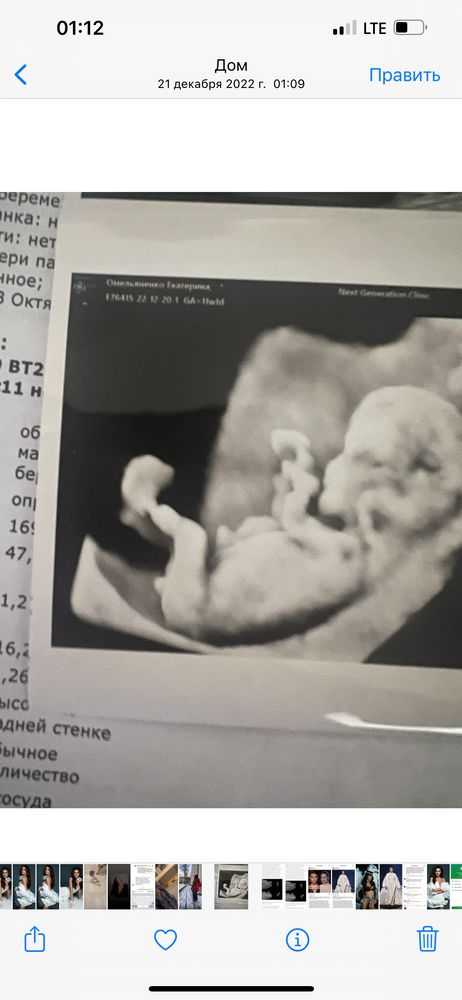

Мальчик девочка?

Мне кажется девочка, бугорок прям между ножек смотрит.... У мальчишек вверх относительно пузика

El, а по фото на кого похоже?) вроде пиписька большая

Иолтло, на 11 недели еще не понятно именно по пипиське так как половые органы еще не сформированы.